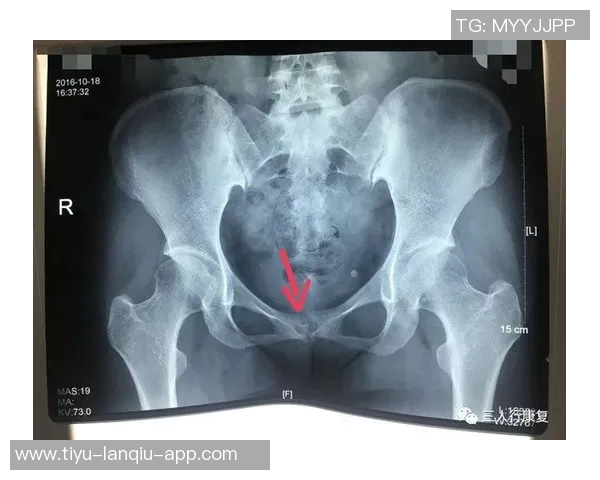

尼科·威廉姆斯是一名备受瞩目的年轻球员,他在比赛中表现出色,为球队贡献了许多关键进球。然而,在一次重要比赛中,他不幸遭遇了耻骨炎。这种疾病给他的训练和比赛造成了严重影响,让他不得不面对漫长而艰难的恢复过程。

初期,尼科并没有意识到自己的伤势有多严重。他依旧坚持参加训练,但随着时间推移,他逐渐感受到身体的不适。经过专业医生的检查后,他被确诊为耻骨炎,这让他深感沮丧,因为这意味着他需要停下脚步,进行长时间的康复治疗。

从确诊开始,尼科·威廉姆斯便积极配合医生制定了一套详细而科学的康复计划。这个计划包括物理治疗、药物调理以及特定动作训练等多个环节,以帮助减轻疼痛和加快康复速度。同时,他也开始注重饮食,通过合理营养来增强身体抵抗力。